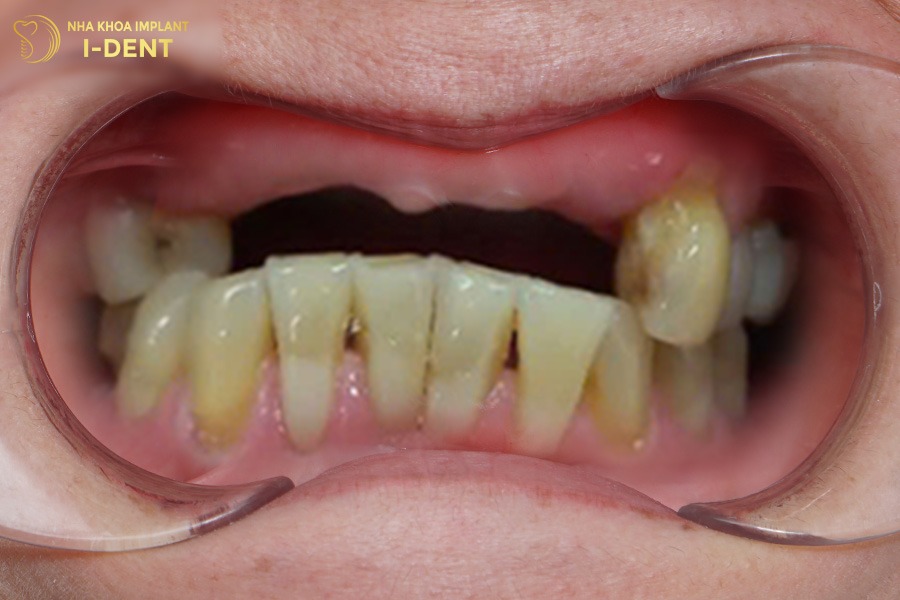

Bệnh nhân gặp nhiều khó khăn trong sinh hoạt và cuộc sống vì mất nhiều răng, hàm trên của chú Sự chỉ còn vài cái răng và cũng bị lung lay nặng. Chưa kể đến tại vị trí răng mất lâu năm còn gặp tình trạng tiêu xương nặng, cùng với đó chú còn có tiền sử mắc bệnh tiểu đường.

Tình trạng răng ban đầu của chú Trương Văn Sự

Nhận định đây là một tình trạng bệnh khá phức tạp, bác sĩ Đình Tín đã thăm khám kỹ lưỡng và đưa ra kế hoạch điều trị chi tiết. Đầu tiên, bác sĩ Tín chỉ định nhổ các răng lung lay, phẫu thuật ghép xương lớn tại những vị trí tiêu xương, sau đó mới tiến hành cấy ghép Implant toàn hàm All-on-4 cho chú Sự. Cuối cùng là phục hình toàn hàm với răng sứ Chrom-Cobalt (Mỹ) trên Implant cho chú.